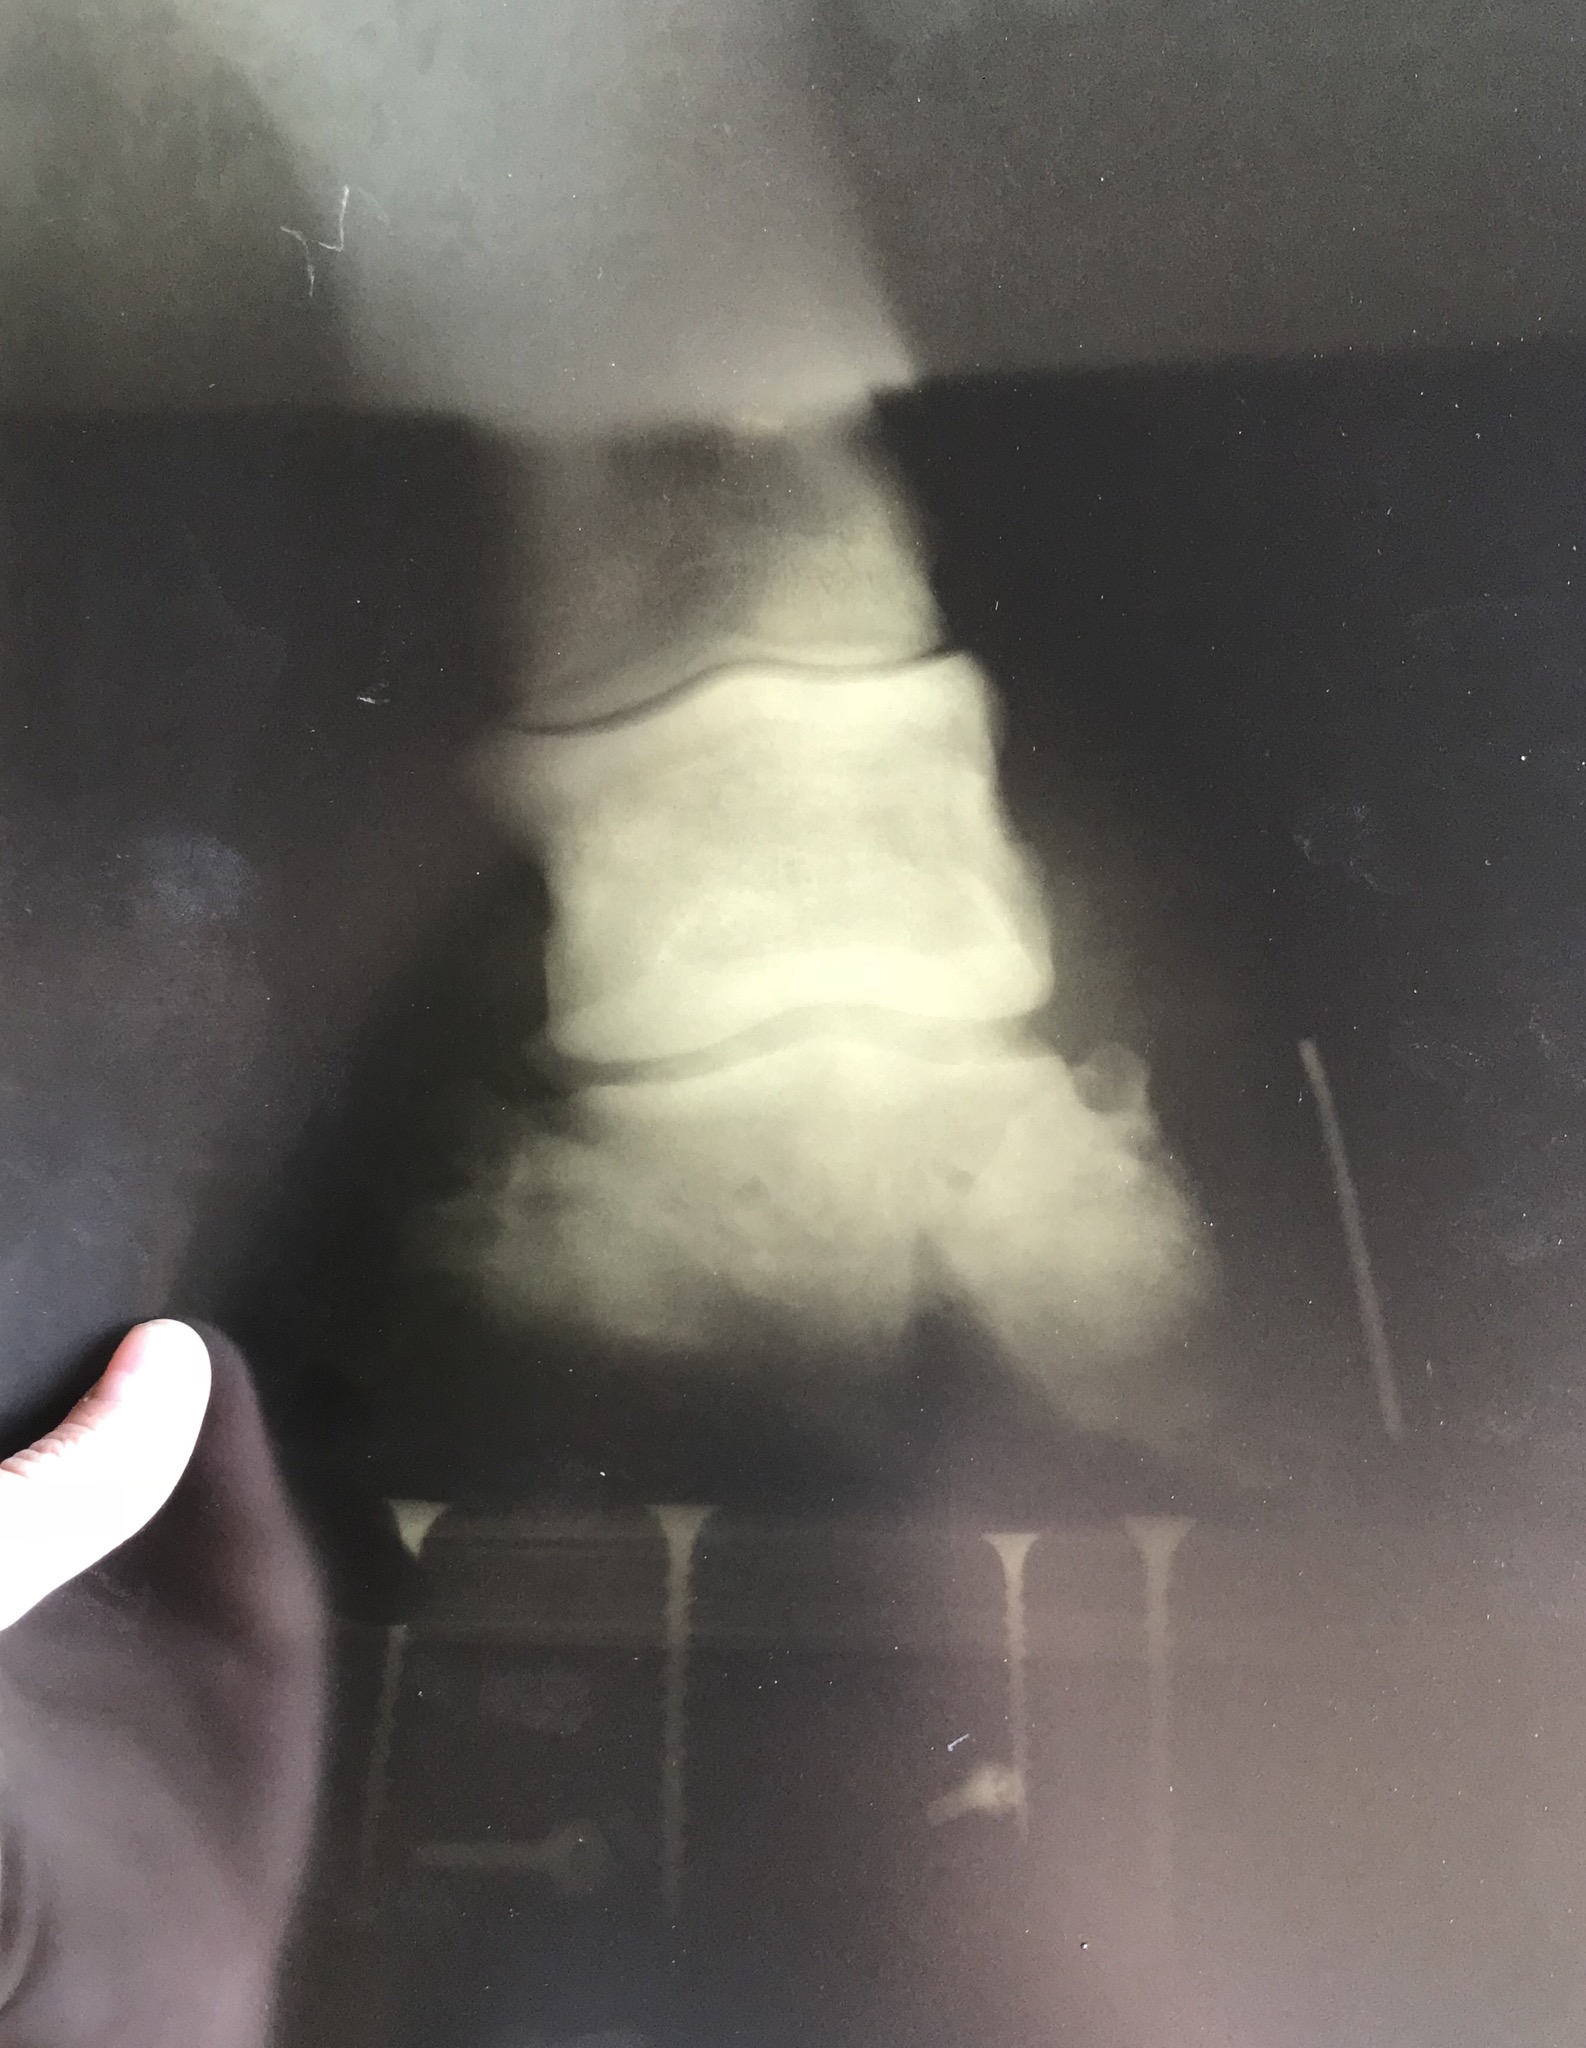

Подскажите пожалуйста, ситуация такова. Купили лошадь из деревни, продавец предупредил что конь каким-то образом обломал некоторую часть копыта переднего, не критично совсем, при этом он не хромал, ничего ему не мешало и не доставляло дискомфорт. В деревне он весь день гулял и жувал траву на мягком, травянистом грунте. Через несколько дней перевезли его к себе в клуб, и видать при перевозке, либо пока шли его грузить (дорога не благоприятная была, камни и тд) возможно намял себе копыто или ещё что-то. На данный момент шагает по мягким грунтам достаточно хорошо, но как только попадётся камешек ,как сразу видно что ему неприятно. Думала над ковкой, но рано. Ему 2,5. Вот думаю как быть, либо может просто не вытаскивать его особо, дать копыту отрасти+подавать подкормки для роста копытного рога. Ещё есть вариант поносить башмаки, пока не отрастет. Но башмаков у нас нет, поэтому если других вариантов не придумаем, будем покупать.